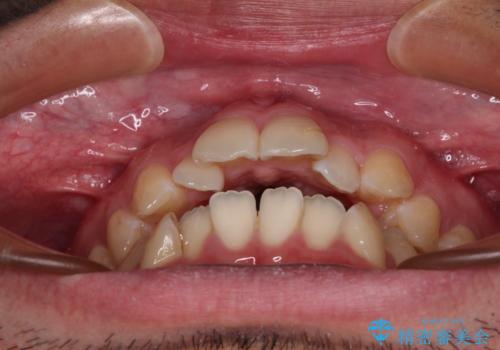

- 前歯の開咬と叢生を気にして来院された患者様です。

開咬の治療は、前歯を閉じるように動かすとともに、上下臼歯を圧下(骨内にめり込ませる)させることで進めて行きます。

インビザラインは臼歯の圧下を効果的に行えるため、インビザラインを用いて矯正治療を行うこととしました。また、アンカースクリューを用いて、口元の突出感の改善を図りました。